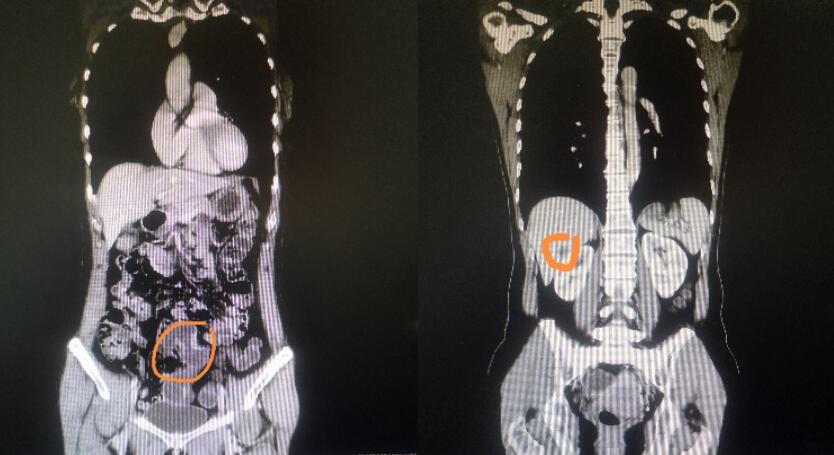

入院后经过详细检查,明确患者为乙状结肠癌并右肝后叶下段肝实质内单发转移瘤(CT如下图所见)。针对患者病情,胃肠外科II科启动多学科会诊(MDT),包括肝胆胰外科、肿瘤科、放射科、病理科团队成员在内。大家充分讨论后为该患者制定了乙状结肠根治性切除+右肝部分切除手术方案。

CT图像(左图是乙状结肠病灶 右图示右肝转移病灶)